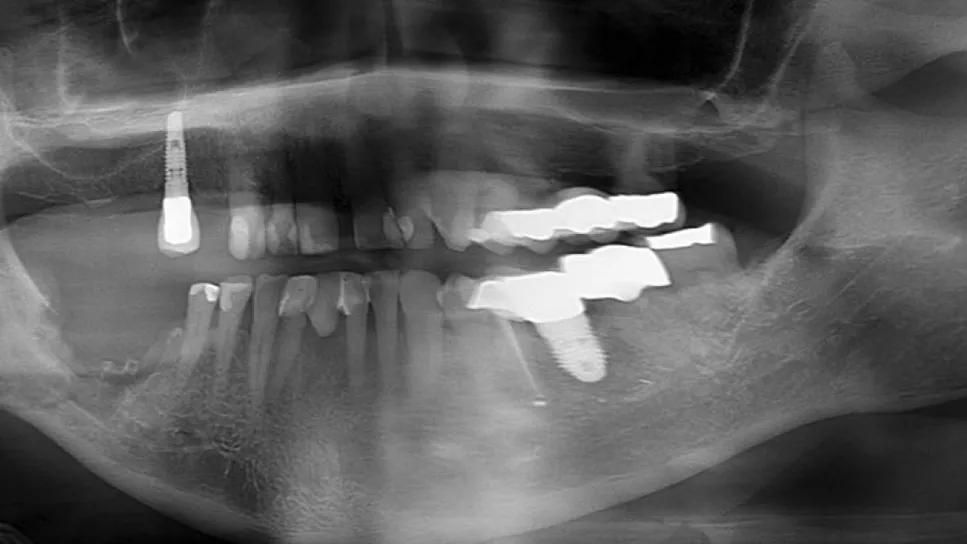

Imaging of Stage IV (“borderline”) preoperative panorex

Stages III and IV are similar, although in Stage III, the MORN extends beyond the IANC but spares > 1 cm height of lingual and buccal cortex. In Stage IV, the MORN extends beyond the IANC, and ≤ 1 cm height of lingual and/or buccal cortex remains with an otherwise intact mandible. Both stages are treated with the rescue flap procedure. Patients who present clinically as Stage IV are classified as “borderline” rescue flap candidates and are consented for both rescue flap and potential segmental resection and osteocutaneous free flap reconstruction. Patients who meet Stage IV criteria intraoperatively and postdebridement are managed with ALTFL rescue flap and concurrent iliac crest cancellous bone grafting. The latter allows for bone growth and preserves the strength and integrity of the mandible.